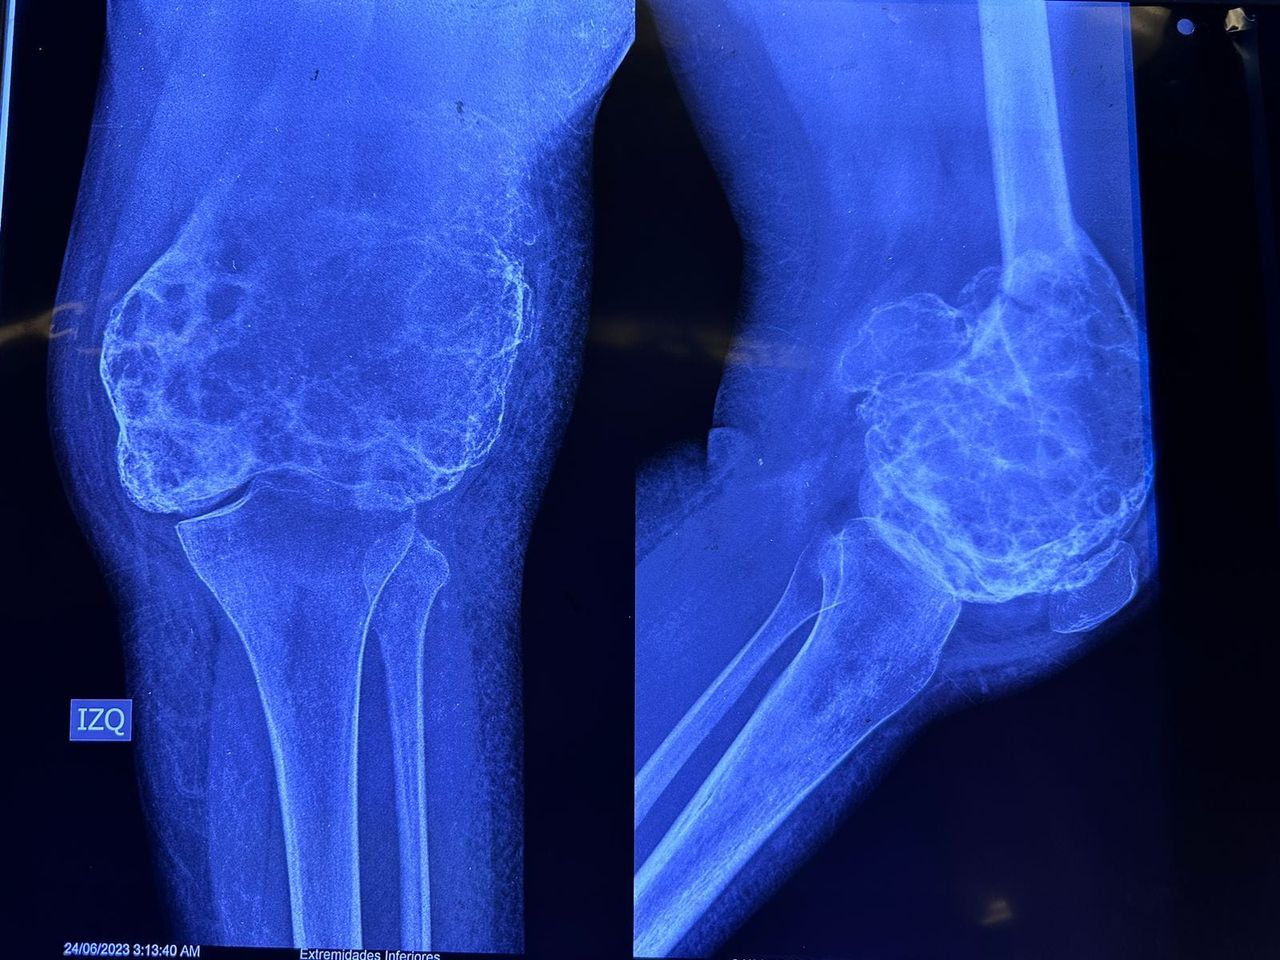

Hola, soy médico egresado de la BUAP y he tenido el honor de especializarme en Traumatología y Ortopedia en el complejo médico Magdalena de las Salinas, IMSS, con la validación de la UNAM. Además, tengo un Máster en Ciencias Médicas, centrado en el área quirúrgica de tumores músculo-esqueléticos, también en la Unidad Médica de Alta Especialidad, Magdalena de las Salinas.

• Tumores oseos

Tumores Músculo Esqueléticos

• Tumores Músculo Esqueléticos Cirugía de rodilla  •